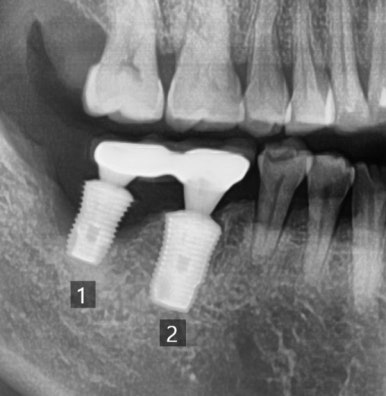

1.흔들리던 임플란트 2. 임플란트 제거 후 3.임플란트 재수술 후

다른치과에서 몇년전에 한 인플란트가 흔들리고 붓는다고 온 분이었습니다.

그림에 1로 표시한 부분은 임플란트 주변을 감싸는 뼈가 많이 녹아서 흔들리고

2로 표시한 치아는 중간 연결고리나사가 부러져서 임플란트 머리도 같이 흔들리는 상태였습니다.

1과 2 임플란트 모두 제거하고

새로 임플란트를 심어 완성하였습니다.